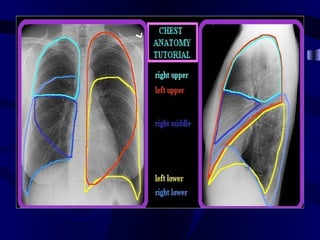

SIGNS OF COLLAPSE

DIRECT SIGNS:

• Displacement of fissures

• Loss of aeration

• Vascular & bronchial signs

INDIRECT SIGNS:

• Mediastinal & Hilar displacement

• Elevation of Hemidiphragm

• Compensatory hyperinflation

Collapse RUL

Collapse LUL